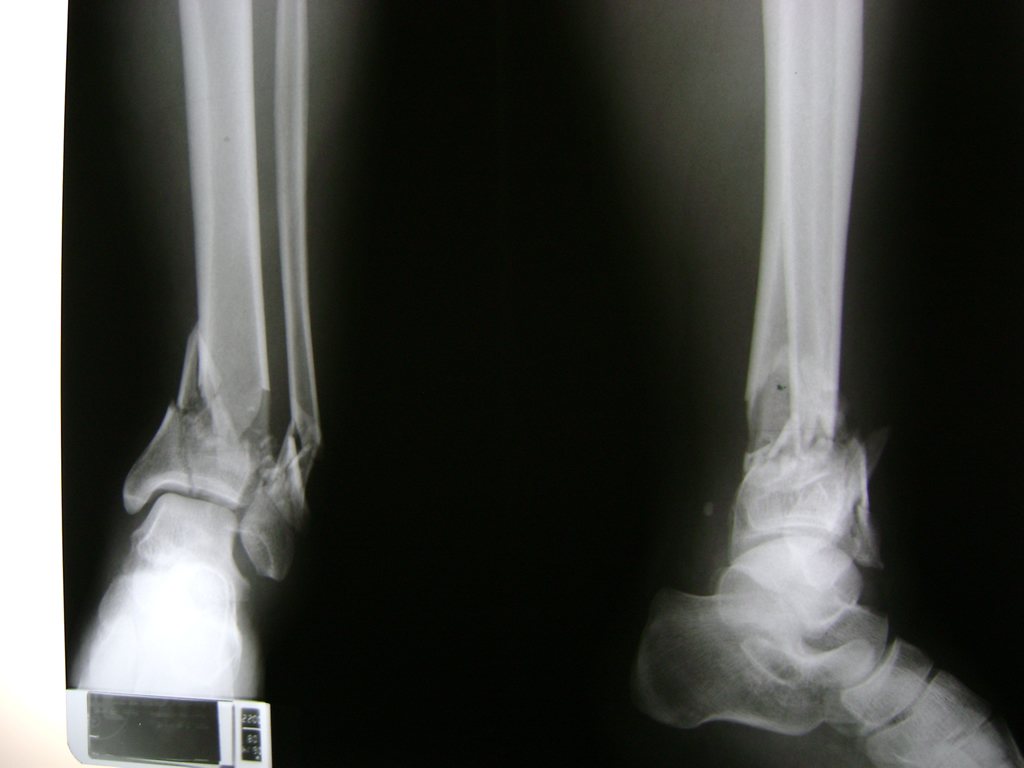

Una fractura de tobillo es la rotura de uno o más de los huesos del tobillo. Estas fracturas pueden ser:

Algunas fracturas de tobillo pueden requerir cirugía si:

- Los extremos de los huesos están desalineados entre sí (desplazados).

- La fractura se extiende hasta la articulación del tobillo (fractura intra-articular).

- Los tendones o ligamentos (tejidos que sujetan los músculos y los huesos entre sí) están rotos.

- El médico cree que sus huesos probablemente no sanen apropiadamente sin cirugía.

- El médico considera que la cirugía puede permitirle una recuperación más rápida y confiable.